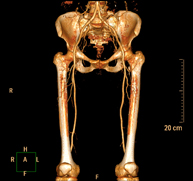

- Angio-TC arterial extremidades inferiores

Prueba diagnóstica no invasiva que consiste en el estudio vascular del sector aorto-ilíaco y de los vasos arteriales de ambas extremidades inferiores obteniendo imágenes de alta definición anatómica mediante el empleo de un equipo de TC Multidetector de última generación y de contraste yodado. La calidad de las imágenes permite realizar reconstrucciones en 2D y 3D gracias a estaciones de trabajo especializadas en el estudio arterial.